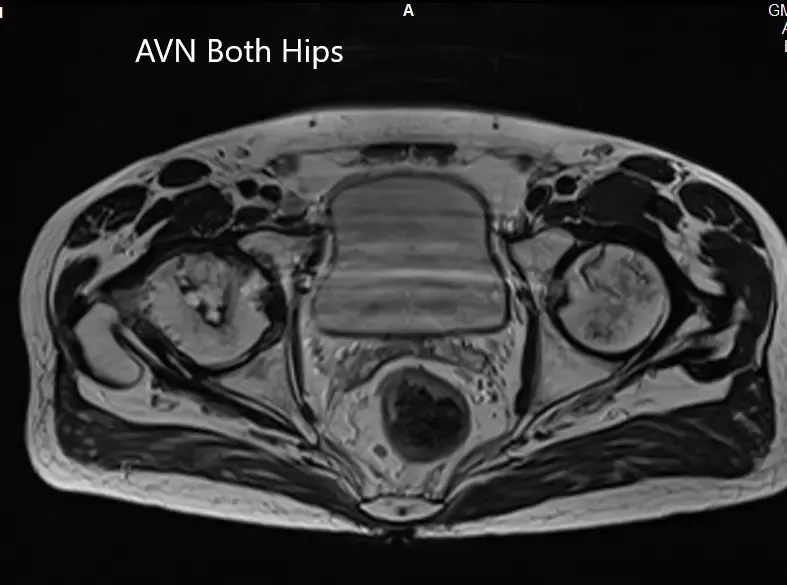

La resonancia magnética sugirió una marcada atenuación de señales en las cabezas femorales bilaterales. Hubo un colapso de la cabeza derecha y un precolapso en la etapa 2a de la cadera izquierda.

Secciones axiales de T1WI y T2WI que muestran AVN bilateral de las cabezas femorales